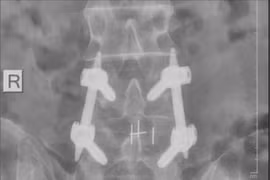

Sau khi vác bao xi măng 50 kg, người đàn ông xuất hiện đau lưng dữ dội, tê bì hai chân, mất cảm giác ngón chân, được bác sĩ xác định thoát vị đĩa đệm cấp, nguy cơ liệt, rối loạn đại tiểu tiện nếu không điều trị kịp thời.